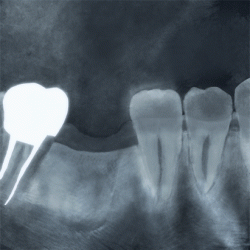

術前レントゲン写真

-